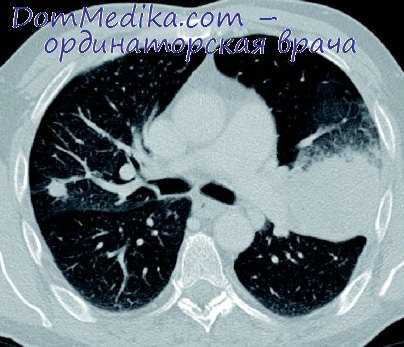

Каждое легкое состоит из нескольких долей: левое - из двух, правое - из трех. Правое легкое крупнее левого.